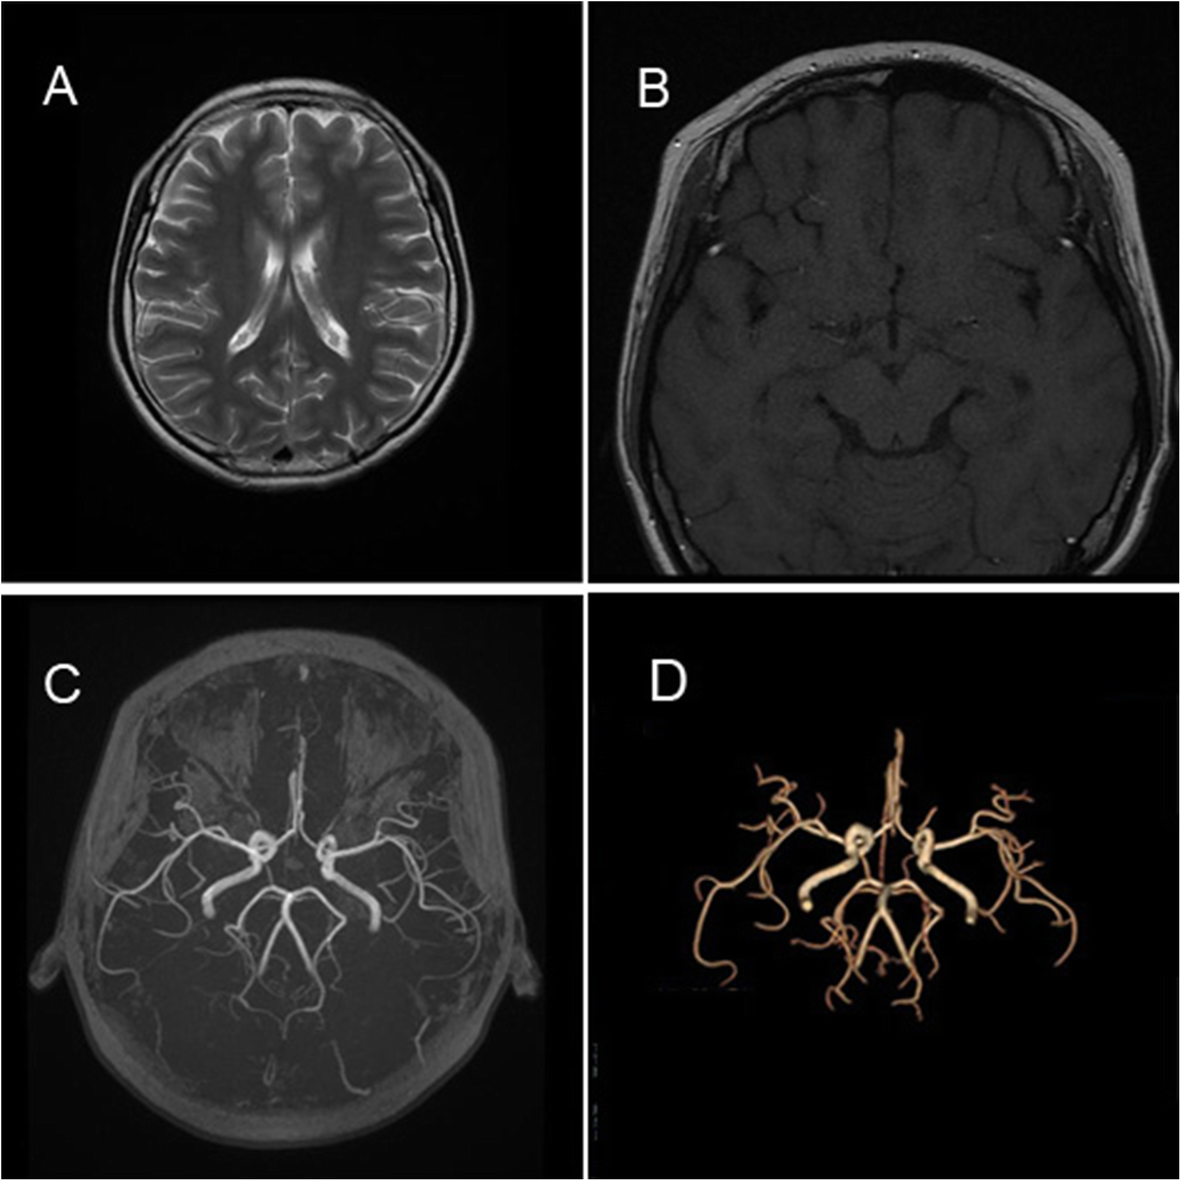

Fig. 2

Neuroimaging. An axial cranial fast spin-echo T2-weighted (a) and T1-weighted (b) magnetic resonance imaging revealed no cerebral calcification or atrophy. Three-dimensional time-of-flight (c) and volume rendering (d) for magnetic resonance angiography demonstrates no intracranial leptomeningeal angiomatosis